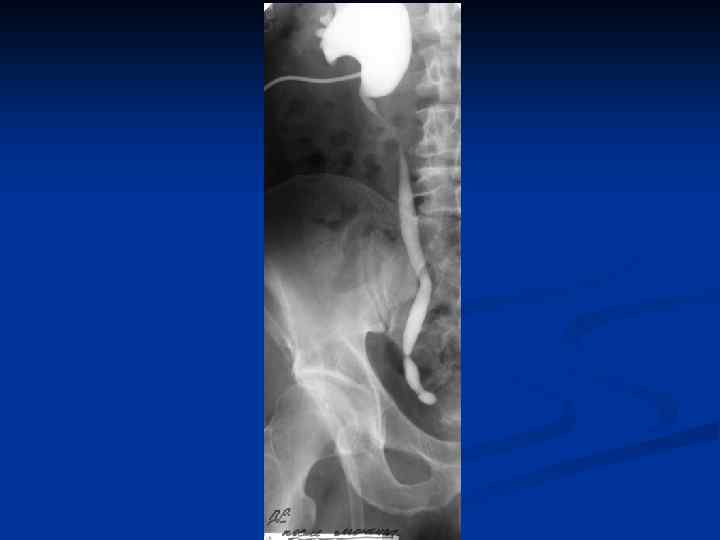

n n n Провести рентгеновское исследование грудной клетки, а если есть показания, то и других органов; Определить туберкулиновую чувствительность; Назначить и провести гистеросальпингографию с 60% раствором водорастворимого верографина, при этом возможно: n n n Определить состояние маточных труб (тонкие, ригидные, запаянные ампулярные отделы, деформация в виде четок, курительных трубок); Выявить форму полости матки, ее размеры, наличие или отсутствие сокращений; Диагностировать наличие / отсутствие рефлюкса контрастного вещества из труб.